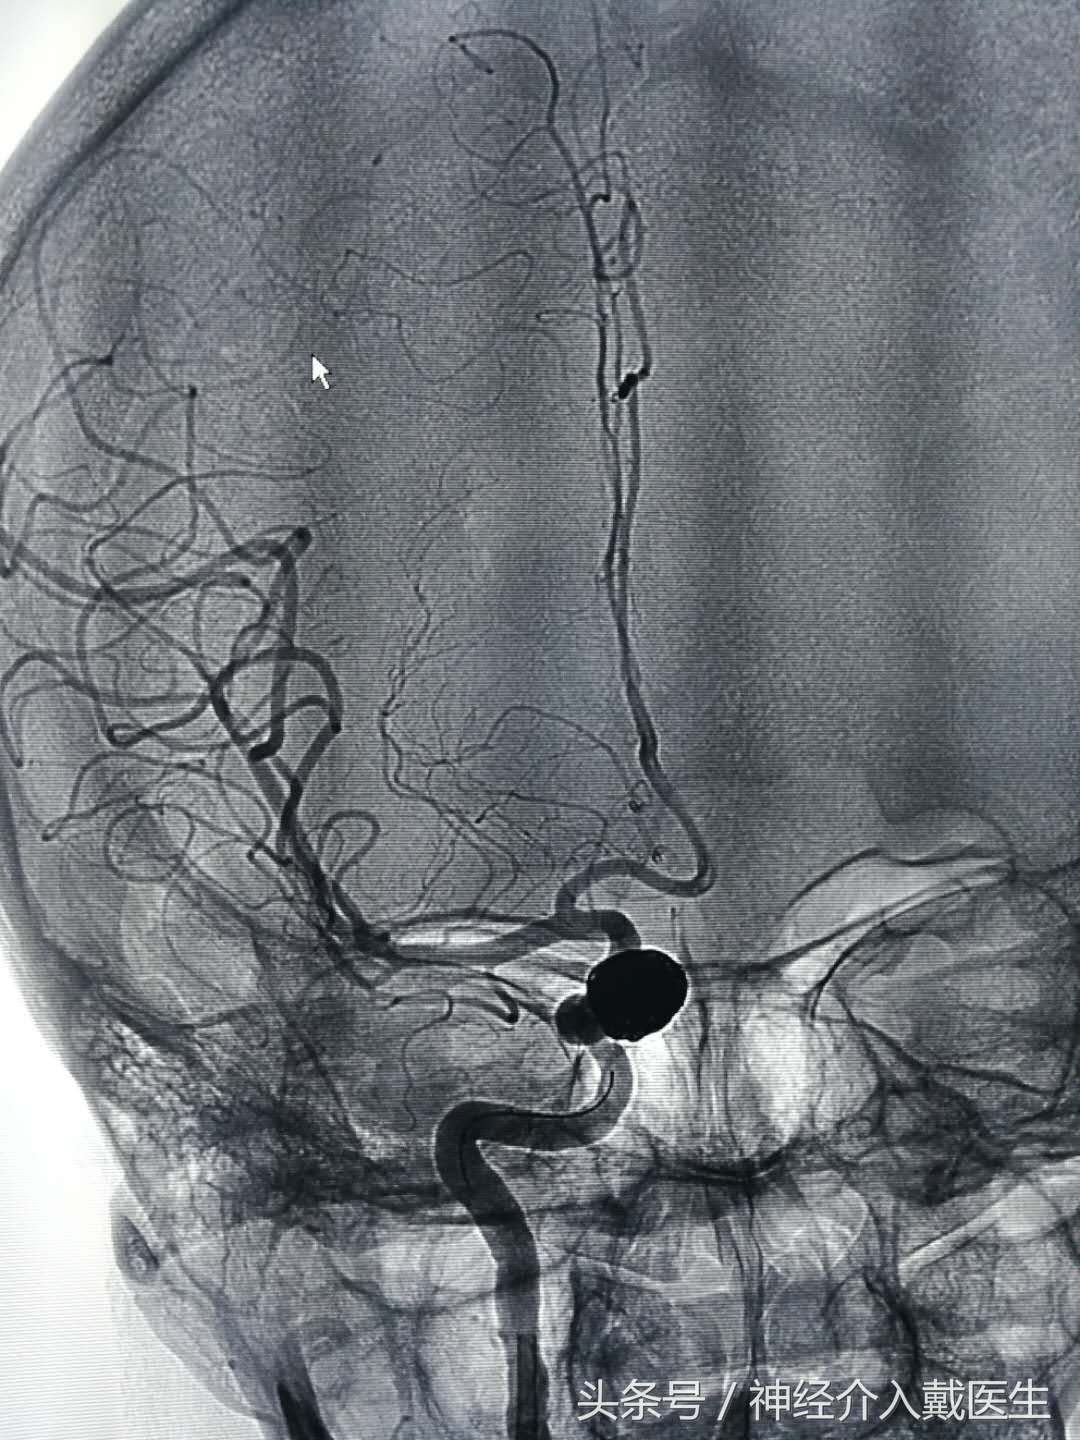

正位像

侧位像